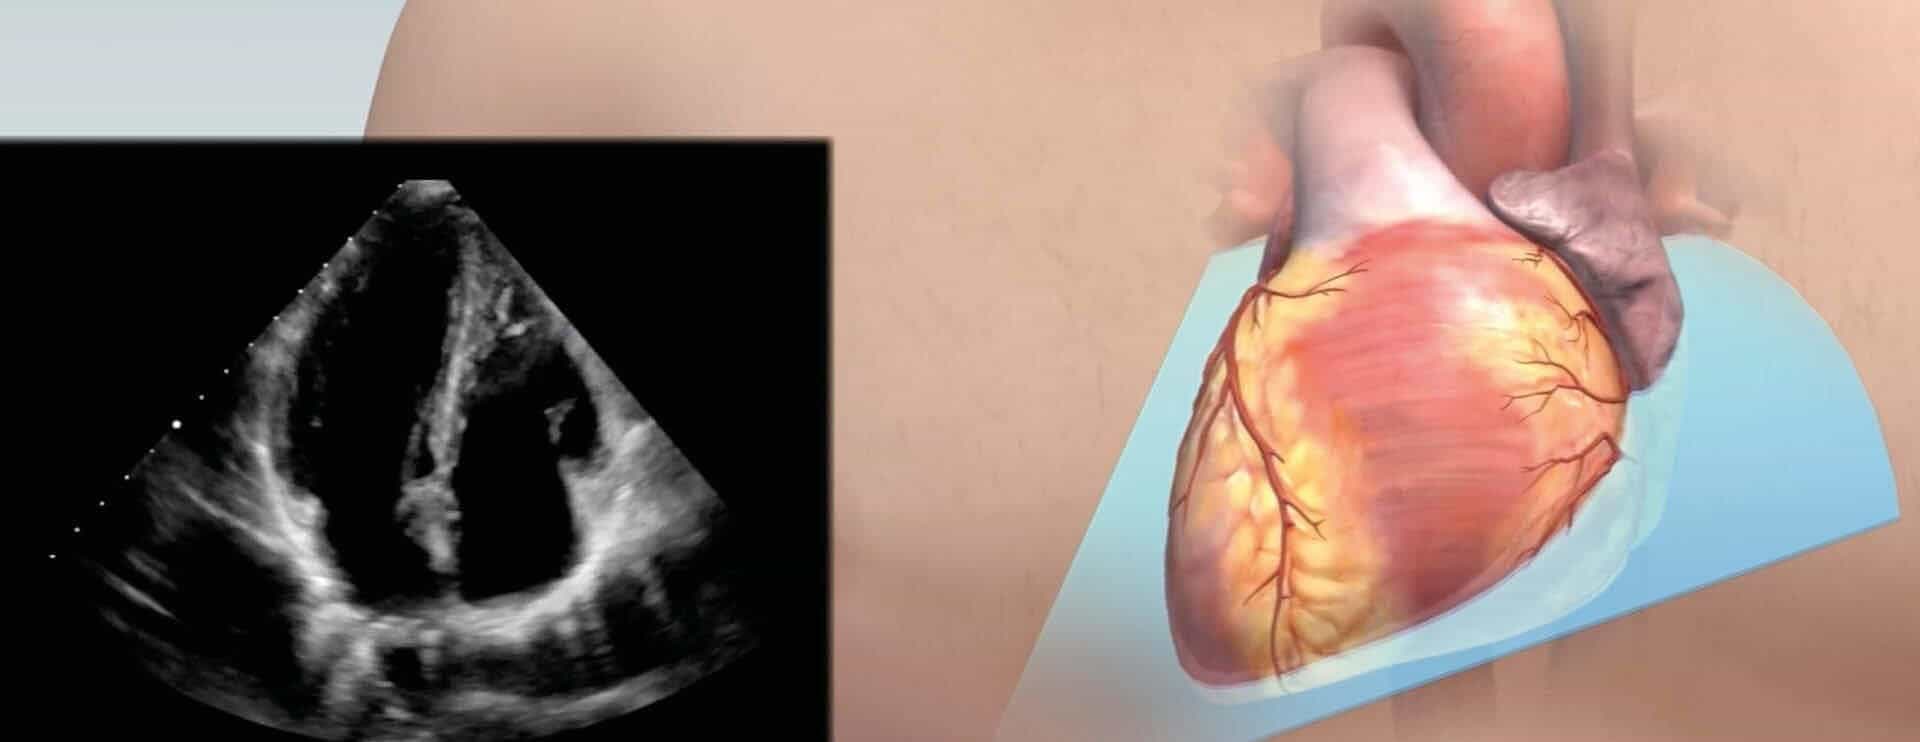

2D Ultraschall: Schnittebenen im Herzen

Bei der transthorakalen Echokardiographie legt der Arzt verschiedene Schnittebenen ins Herz. Dadurch kann der Untersucher alle Abschnitte des Herzmuskels, die Herzklappen und auch großen Herzgefäße durch die Brustwand untersuchen. Die nachfolgende Abbildung zeigt, welche Einblicke die unterschiedlichen Schall-Ebenen ermöglichen.